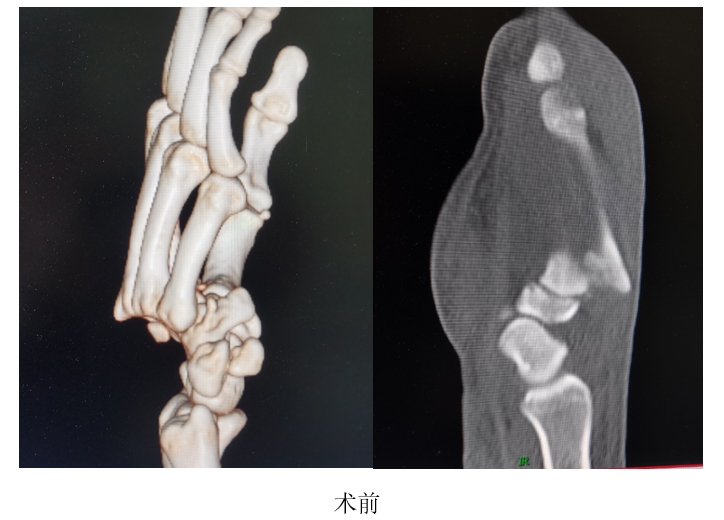

张先生在国外时意外碰伤右手,造成右手第2-5腕掌关节脱位合并多处腕骨骨折和韧带损伤,在当地医院多次尝试复位,均未能成功,由于损伤严重,大量出血,肢体肿胀严重,张先生寝食难安,精神萎靡。经朋友联系介绍,张先生返回国内,来到我院郑州院区手外显微骨一科就诊。反反复复的复位、长时间的飞行进一步加重了张先生患肢的肿胀,在到达我院郑州院区的时候甚至出现了手指没有感觉的症状。赵治伟主任判断,这是骨筋膜间室综合征的表现,如果任其发展,张先生患者可能要面临肢体坏死甚至是截肢的风险。于是,赵治伟主任迅速组织科室人员,为这位患者开辟绿色通道,安排了急诊手术。经过积极地治疗和精心护理,患者目前恢复良好。